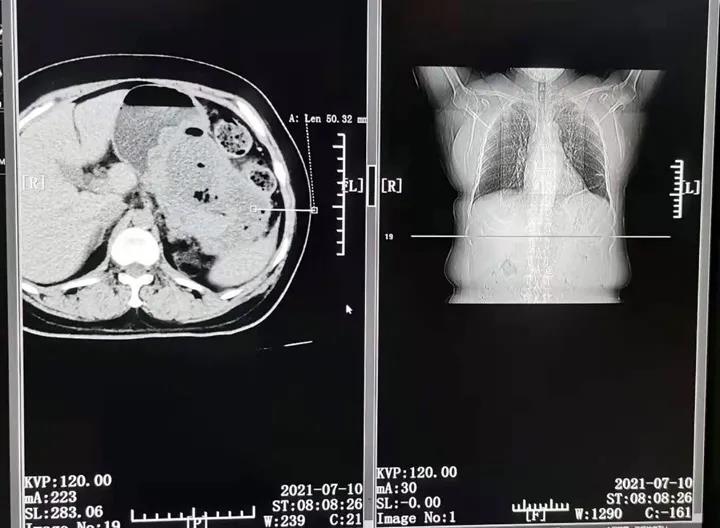

患者,沈某,女 48岁,发烧高达40度,以肺炎收入我院。CT显示胰腺7.5cmx5.9cmX9.5cm脓肿,经抗炎治疗,仍高烧不退。后经普外科、中医科、超声科反复会诊讨论,考虑到患者腹部脓肿部位的特殊性(四周被肠管、胃、肝、脾、大血管包绕),操作必须精准,需要实时监控,建议介入治疗。决定由放射科和超声影像科联合为该患者实施“行超声导向下,经皮穿刺、腹腔脓肿抽吸、引流术”。

13日下午15时,县医院超声科主任邢敏和放射科主任杨光远紧密合作,在相关医技、护理人员配合,在患者完全清醒的状态下,用时20分钟,成功的为患者抽出腹腔内深藏的乳白脓液,并置入一根专用引流管引流。术后患者在家属搀扶下自行走回病室,当晚高烧即退,且无明显不适。